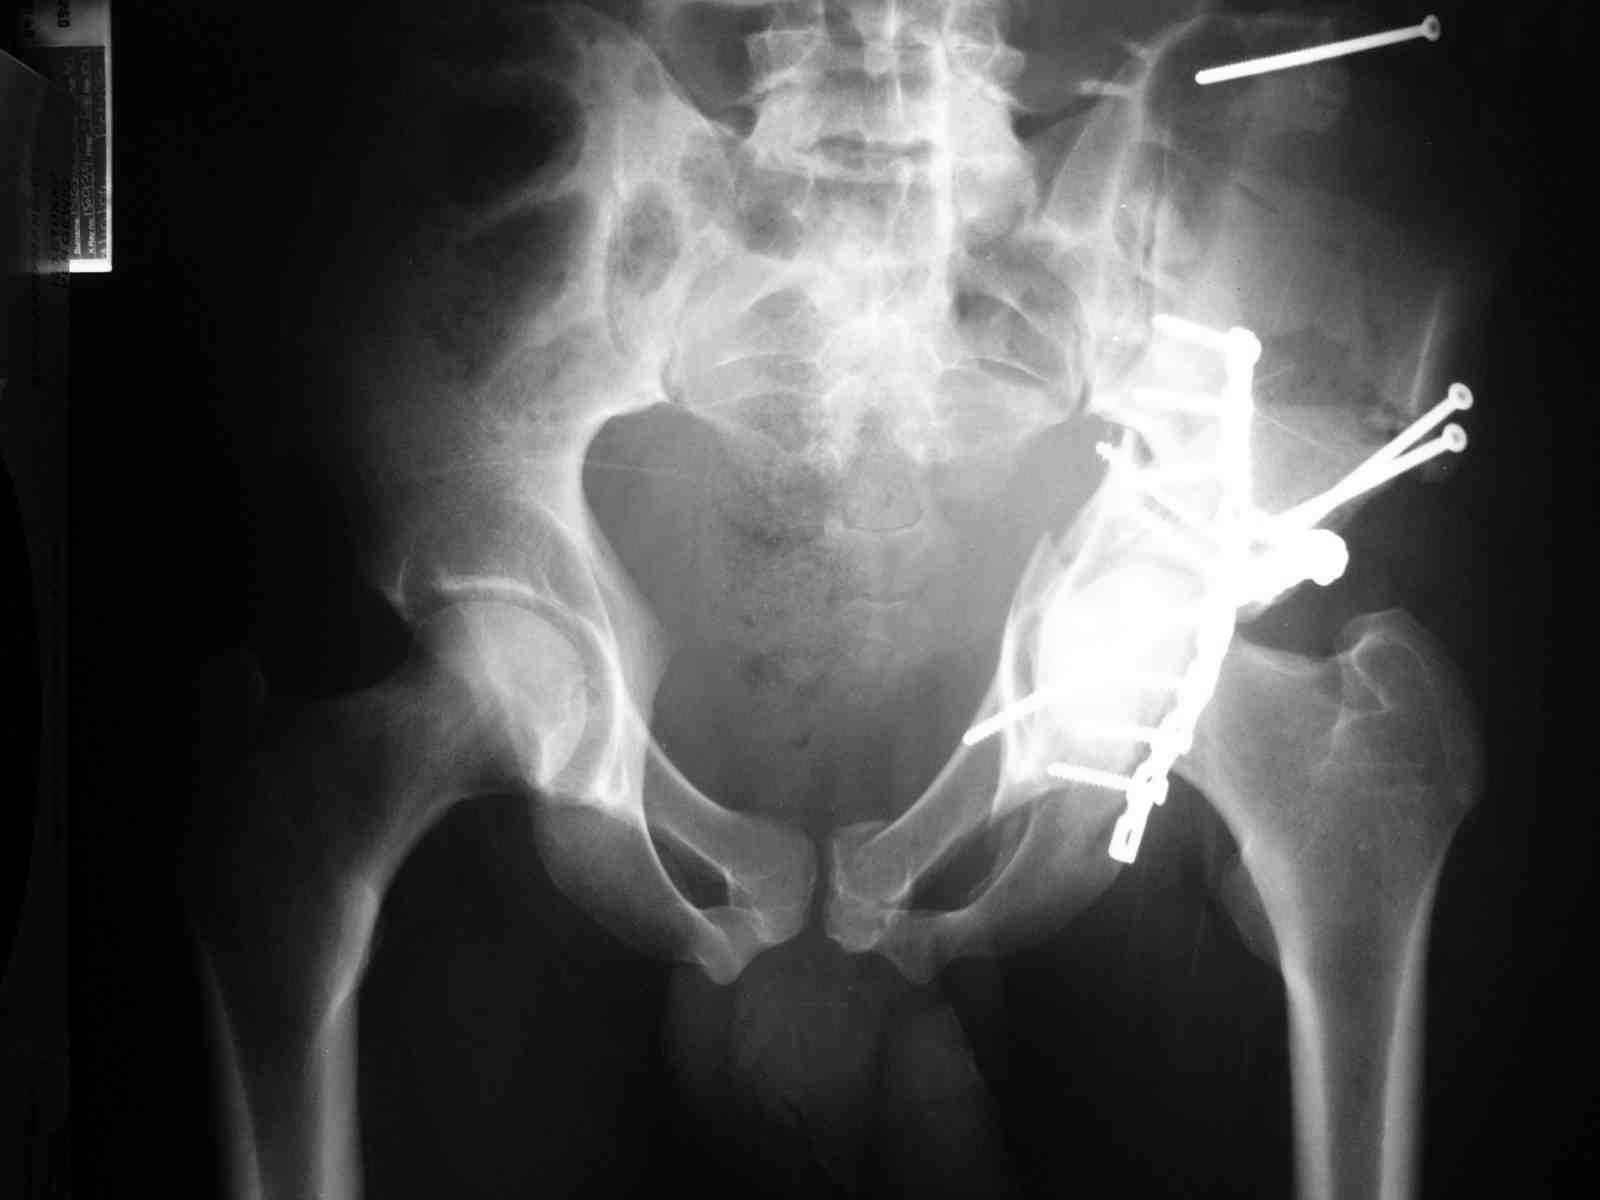

Спасибо за комментарии и рекомендации. Откровенно говоря, больного я прооперировал на прошлой неделе, через 5 дней после аварии и проблем с ним пока никаких нет, на удивление при достаточно обширной диссекции (илиофеморальный доступ) болей практически нет, так что больной самостоятельно садится в кровати, выполняет активные движения в оперированном суставе, сгибая до 60 градусов пока, далее с ассистенцией.

Причиной обращения к сообществу были возникшие непосредственно после операции сомнения и разочарования полученным качеством репозиции: а надо ли было трогать перелом вообще, репозиция передней колонны технически была очень сложна для меня, хотя реконструкции была в той же последовательности, что Д-р А.В.Рунков рекомендовал, в какой-то момент безуспешных манипуляций стал думать о *вторичной конгруэнтности*, которую не так давно обсуждали на

форуме и скелетном вытяжении. С репозицией и фиксацией задней колонны и отдельно задне-верхней стенки впадины проблем не возникло. Послеоп. Рг граммы в приложении. Если возникнут какие-либо дополнения или поправки - был бы признателен.